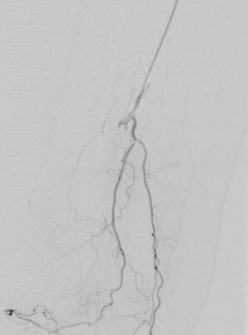

7. 术后造影血流恢复

本例患者股浅动脉重度闭塞,股浅远端重度钙化病变近收肌管,利用Shockwave冲击波球囊获得满意的管腔准备后联合使用DES,为保障远期通畅植入支架,支架膨胀形态理想。